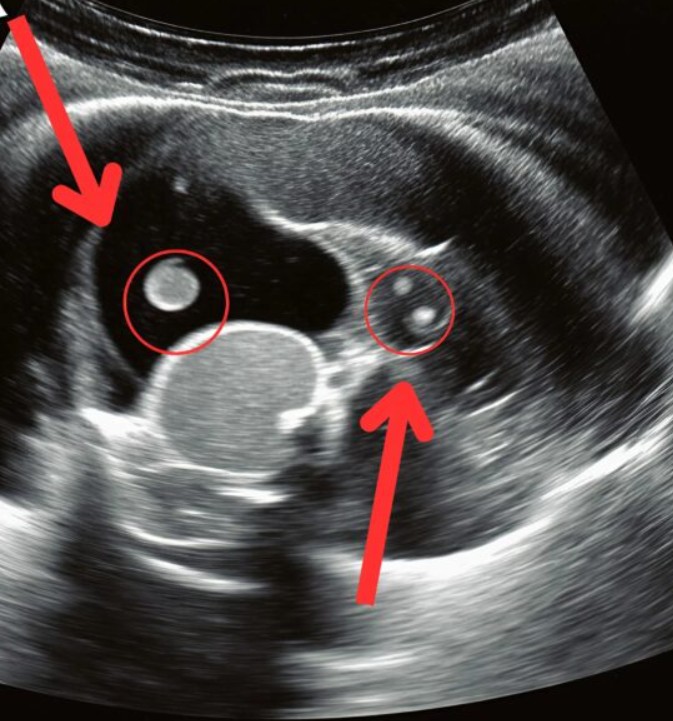

Acil servis koridorlarında zaman buz kesti. Kızım sedyede acı içinde kıvranırken doktorların endişeli bakışları altında ultrason sonuçlarını bekledik. Sonunda doktor yanımıza gelip o hiçbir ebeveynin duymak istemediği cümleyi kurdu: “Acil ameliyat gerekiyor.” Meğer o sırt ağrıları sandığımız gibi çantadan değil, sessizce büyüyen bir böbrek taşından kaynaklanıyormuş. Taş yerinden oynayıp kanala düştüğü için şiddetli sancı ve hayati risk oluşturmaya başlamıştı.